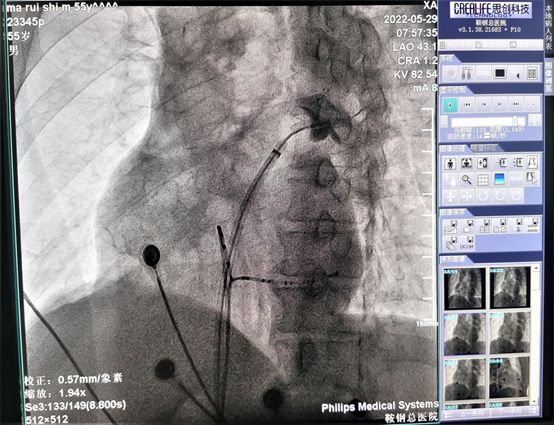

这两例房颤患者均曾就诊于我院房颤门诊,其中一例为阵发性房颤,症状反复发作,药物治疗效果不佳;另一例为持续性房颤,病史小于1年,病人有积极的治疗意愿。两名患者顺利完成房颤冷冻消融手术,术中房颤心律成功转复窦性心律。